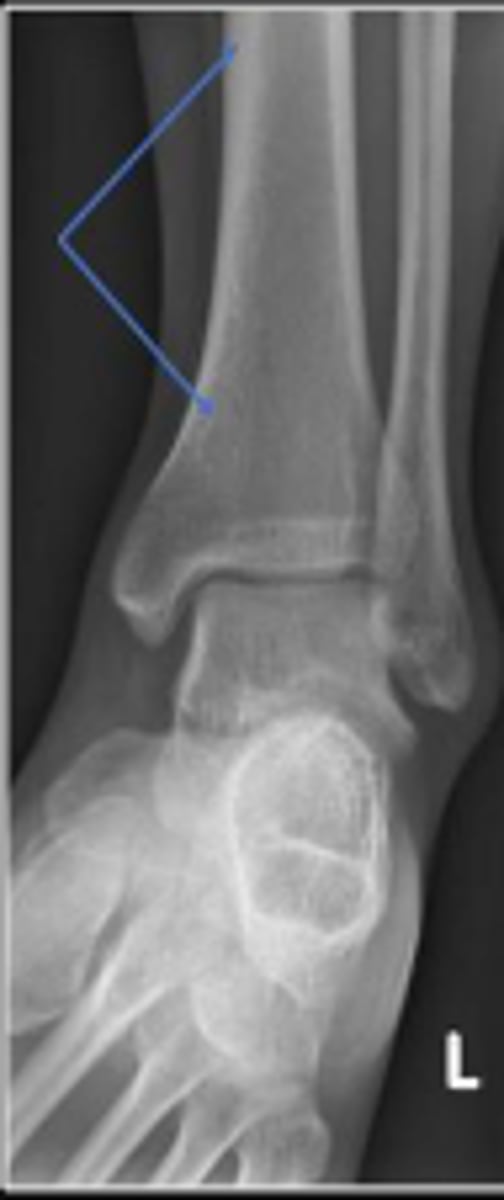

Axial relationship of the ankle

What is the overarching name of the assessment?

Tibial angle & fibular angle

What are the 2 components of the assessment?

Tibial angle

What is the name of the assessment?

Yes

Is the assessment within normal limits?